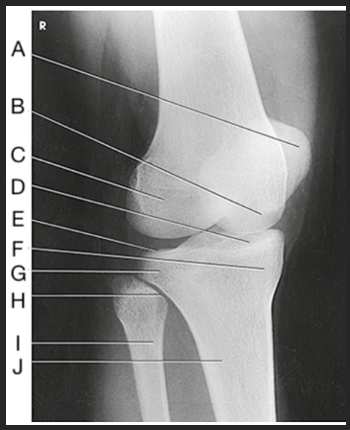

Name this projection

AP oblique medial rotation

What is demonstrated?

Lateral aspect (distal femur, patella, lateral tibial condyle, fibular head, and proximal tibiofibular joint)

What joint is demonstrated?

Proximal tibiofibular joint

Label the image: A

patella

Label the image: B

medial femoral condyle

Label the image: C

lateral femoral condyle

Label the image: D

medial tibial plateau

Label the image: E

Lateral tibial plateau

Label the image: F

medial tibial condyle

Label the image: G

lateral tibial condyle

Label the image: H

tibiofibular articulation

Label the image: I

fibula

Label the image: J

tibia